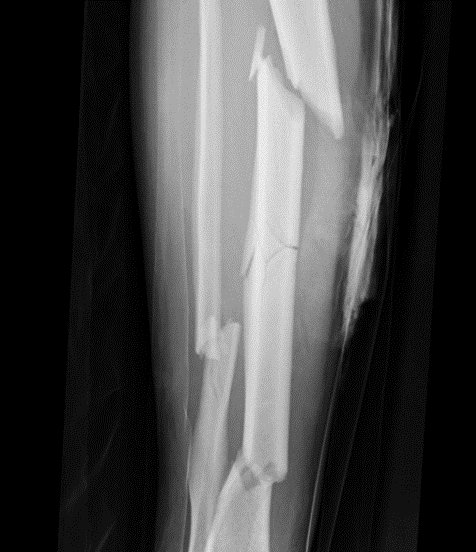

What type of fracture is this?

Butterfly

Forms a triangular shape